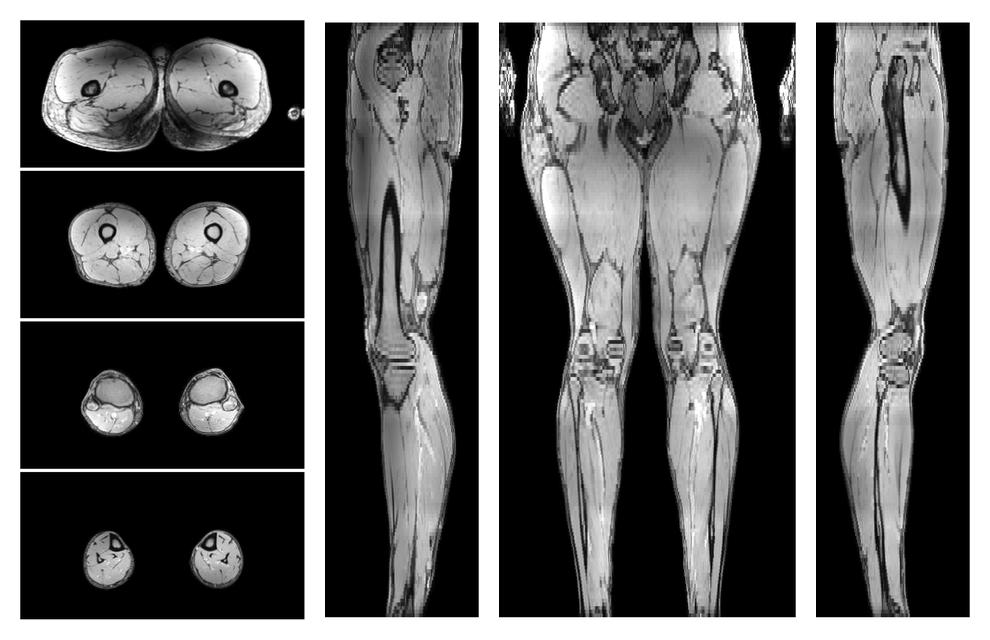

Muscle fiber tractography

Whole leg muscle fiber tractography using DTI, for information look here».

• 3D volume renders of muscle fiber tractography

Whole leg 3D fiber tractography of all muscles segmented using a CNN UNET.

• Muscle fiber length map

Muscle fiber tract length map based on whole leg DTI based fiber tractography.

• Muscle fiber angle map

Muscle fiber tract angle map based on whole leg DTI based fiber tractography.

• Muscle fiber density map

Muscle fiber tract density map based on whole leg DTI based fiber tractography.

• Muscle fiber curvature map

Muscle fiber tract curvature map based on whole leg DTI based fiber tractography.